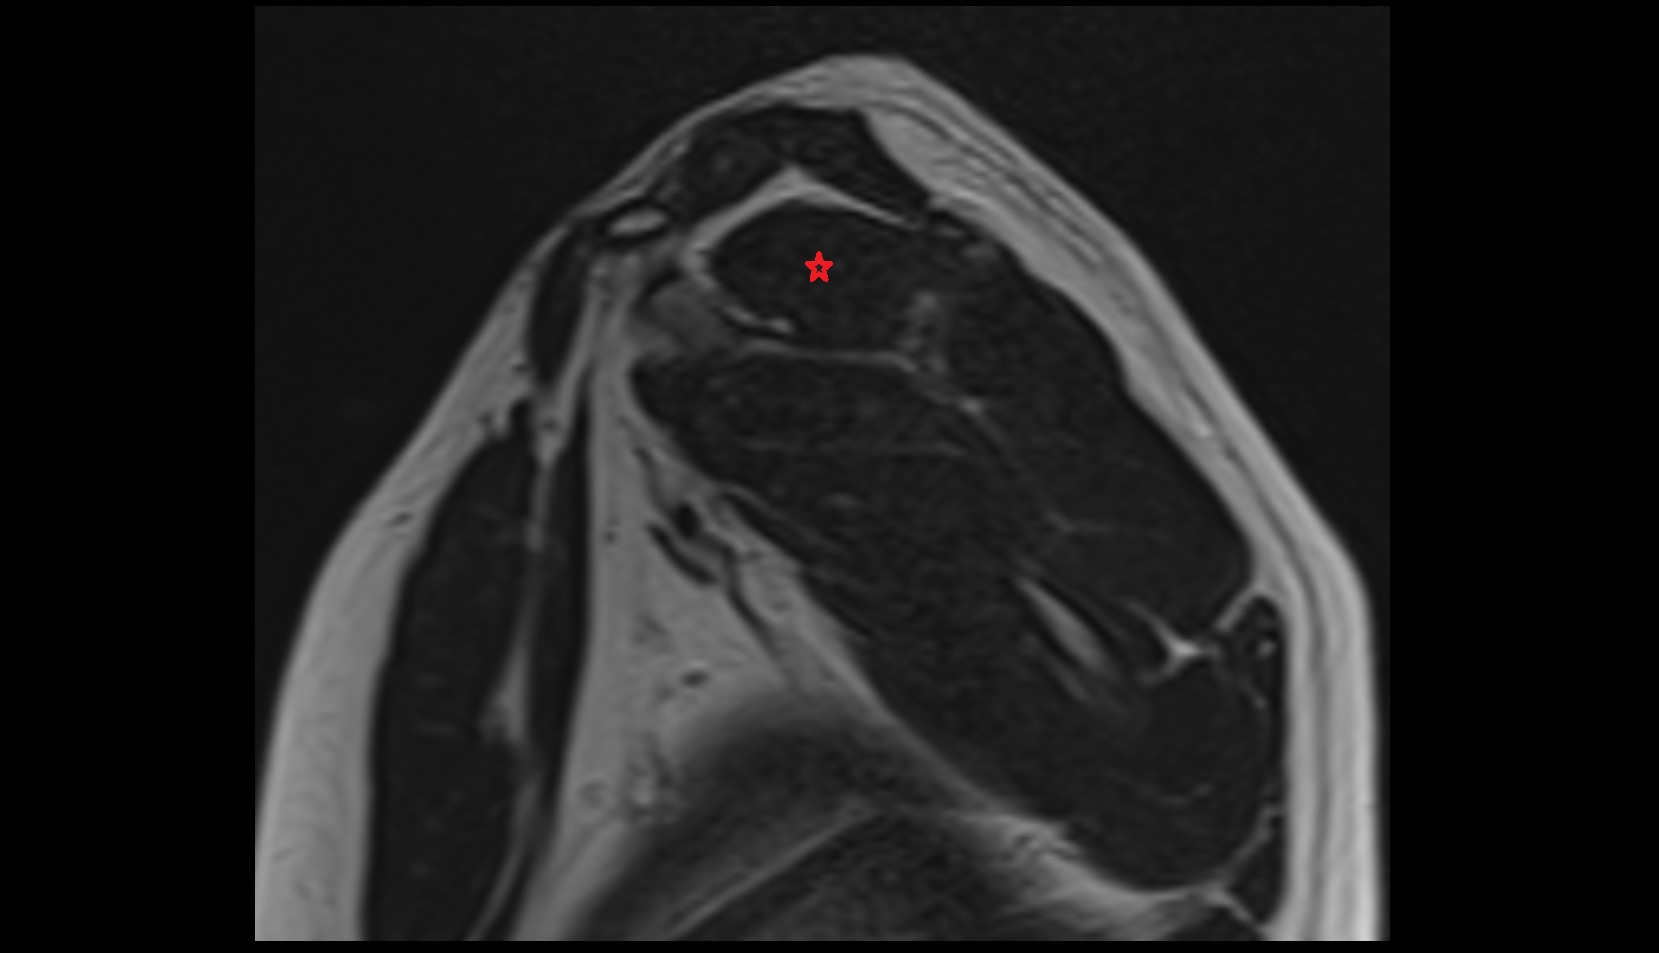

- Shoulder joint (glenohumeral joint)

- Supraspinatus tendon

- Glenoid labrum

- Adipose tissue (Shoulder)